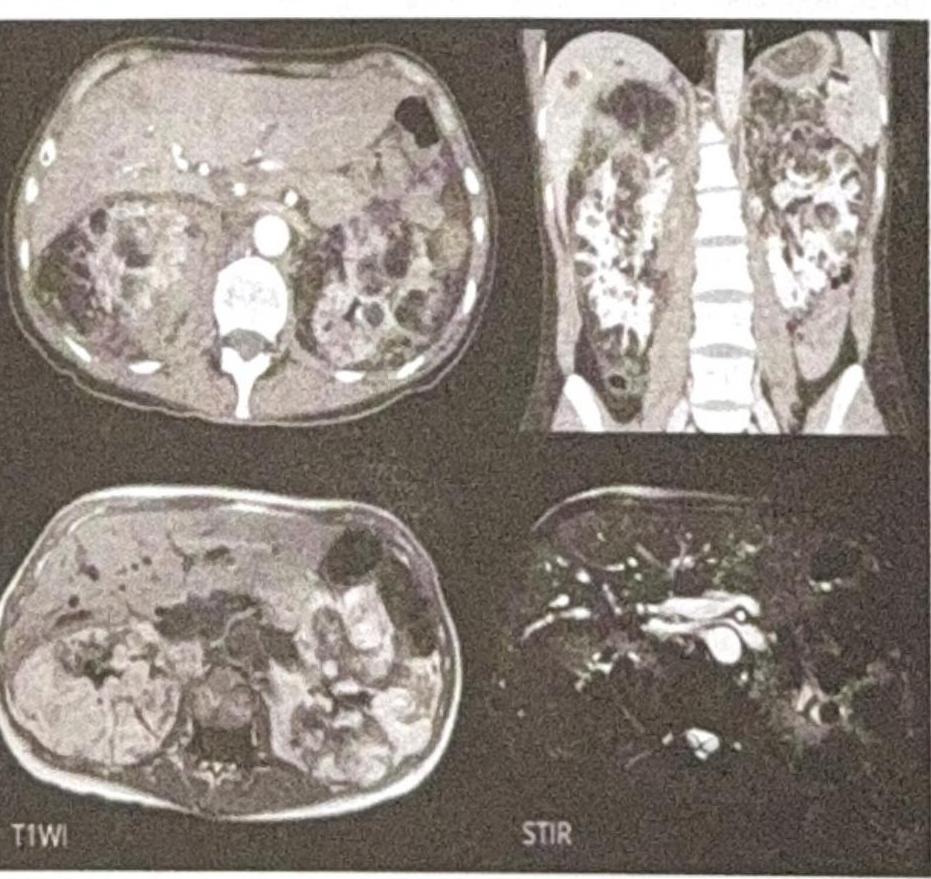

What is the Diagnosis based on the CT Scan given below?

Explanation: ***Polycystic kidney disease*** - The CT scan images show **enlarged kidneys** replaced by numerous **cysts of varying sizes**, which is the hallmark appearance of polycystic kidney disease. - The presence of multiple cysts **bilaterally** and diffusely throughout the renal parenchyma is characteristic of this genetic disorder. *Renal cyst* - A single renal cyst is a common benign finding, appearing as a **well-defined, fluid-filled** structure. - The images clearly demonstrate **multiple cysts** affecting both kidneys, ruling out a solitary renal cyst. *Renal tumor* - A renal tumor (e.g., renal cell carcinoma) typically appears as a **solid mass**, often with heterogeneous enhancement after contrast. - The lesions seen in the image are predominantly **cystic** and multifocal, which is inconsistent with a typical renal tumor. *Renal angiomyolipoma* - Renal angiomyolipomas are benign tumors containing **fat, smooth muscle, and blood vessels**, and they characteristically show **macroscopic fat** on CT scans. - While they can be multiple, especially in tuberous sclerosis, the dominant feature in the image is widespread cystic transformation, not fat-containing solid masses.